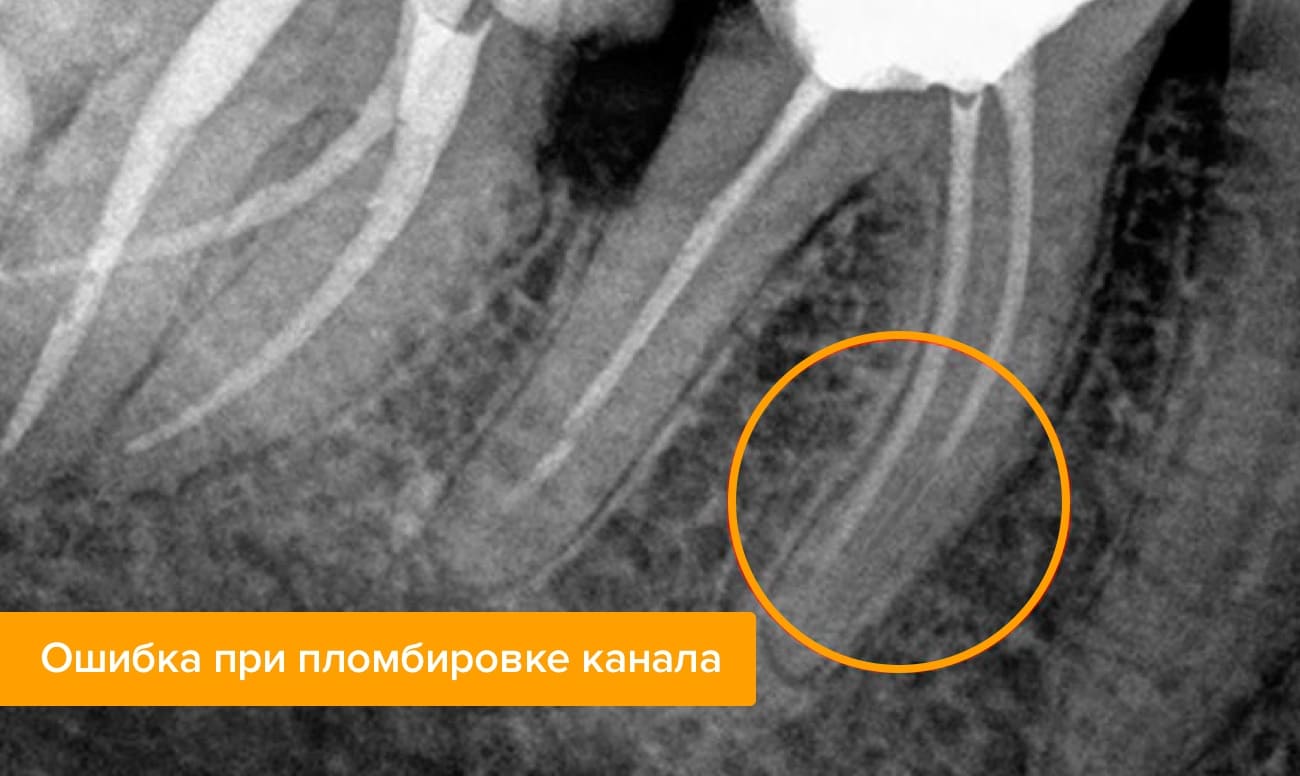

Каналы не полностью закрыты пломбировочным материалом

Если врач ошибся, оценивая глубину каналов, и не запломбировал их полностью, то со временем в пустотах могут скопиться бактерии и спровоцировать воспалительный процесс. Такая ошибка проявляет себя не сразу: довольно долго пациенту может казаться, что все хорошо. Однако деструктивные процессы рано или поздно все равно проявятся — как правило, резкой болью, которая появляется сама по себе или при надавливании на зуб. Воспаление в незакрытом канале может привести к разрушению корня зуба, образованию гранулемы или кисты.

На рентгеновском снимке виден участок канала, где осталась пустота, без пломбировки